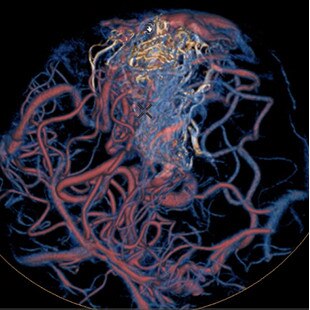

Planifier

Guider

Évaluer